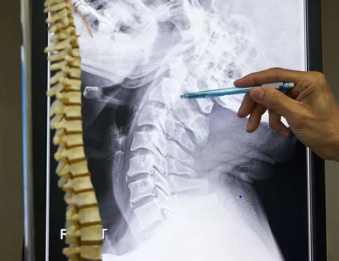

목디스크, 즉 경추 추간판 탈출증은 목 뒷부분의 척추인 경추와 경추 사이의 디스크가 손상되어 신경을 압박하거나 자극하는 질환입니다. 이는 다양한 증상을 유발할 수 있으며, 적절한 치료를 받지 않을 경우 심각한 결과를 초래할 수 있습니다. 목디스크의 치료 방법은 크게 비수술적 치료와 수술적 치료로 나뉩니다.

1. 경추 전방 고정술 (ACDF): 목 앞쪽에 작은 절개를 하여 파열된 디스크에서 신경을 누르는 부분을 제거한 후, 디스크 공간을 뼈 이식 등으로 채워 융합을 시도합니다.

2. 인공 경추 추간판 전치환술: 손상된 디스크를 제거하고 그 자리에 이동식 장치를 삽입하여 디스크의 움직임을 모방합니다.

3. 후방 경추 디스크 절제술: 목 뒤쪽에 절개를 하여 척추 신경을 압박하는 파열된 디스크 부분을 제거합니다.

4. 미세 현미경을 통한 디스크 절제술: 목 뒤쪽에 작은 절개를 하여 뼈의 일부를 제거하고 신경근 및 디스크를 노출시킨 후 파열된 디스크를 제거합니다.